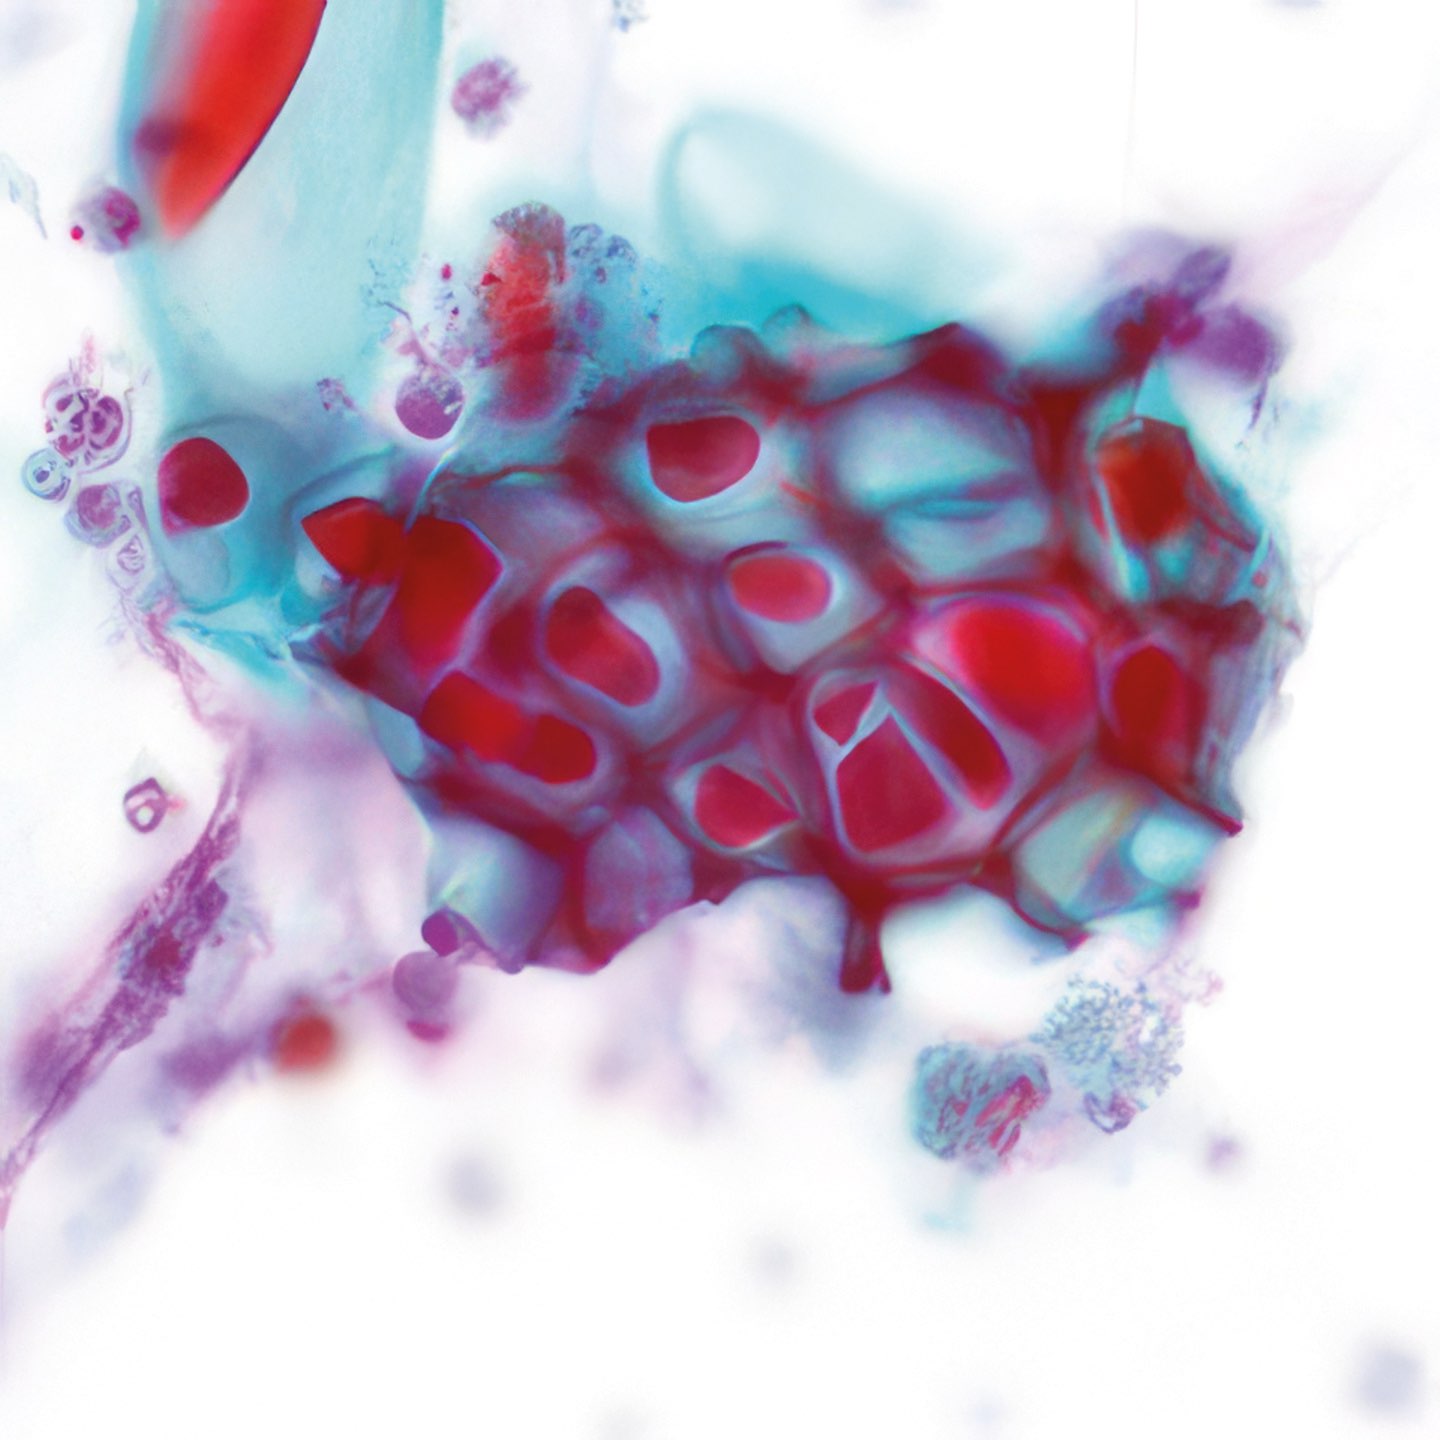

Abbildungen 2 - 4: Pap-Färbung, Obj. 40x.

Onkozytisches Adenom 1

Die zytologischen Abb. 2-4 zeigen dieselben Zellen. Das Zytoplasma ist breit fragil und enthält massenhaft feine eosinophile Granula. Die relativ grob strukturierten Kerne variieren in Größe, sind aber einheitlich rund, zeigen keine Kerben und enthalten einen gut erkennbaren Nukleolus.

Die eosinophilen Granula im Zytoplasma der Zellen entsprechen einer

dichten Ansammlung von Mitochondrien und gleichen damit den das Hormon

Calcitonin produzierenden para-follikulären Zellen der Schilddrüse. Diese

onkozytischen Tumoren wurden früher als Hürthle-Zell-Tumoren

bezeichnet.

Es gibt eine gut- und eine bösartige Variante (Adenom und Karzinom), die

zytologisch meist nicht zu unterscheiden sind und nur die Diagnose

„follikuläre Neoplasie, Bethesda IV“ erlauben. Auch histologisch ist

die Unterscheidung oft schwierig.

Makroskopisch handelt es sich im vorliegenden Fall um einen etwas über

2 cm messenden, von einer dünnen Kapsel eingeschlossenen Tumor (Abb.

5). Zytologisch sind weder Mitosen noch Kernkerben nachweisbar.

Histologisch konnten weder ein Kapseleinbruch (Abb. 6 u. 7), noch eine

Gefäßinvasion, noch papilläre Strukturen nachgewiesen werden. Das sind

Hinweise auf mehrjährige Rezidivfreiheit.